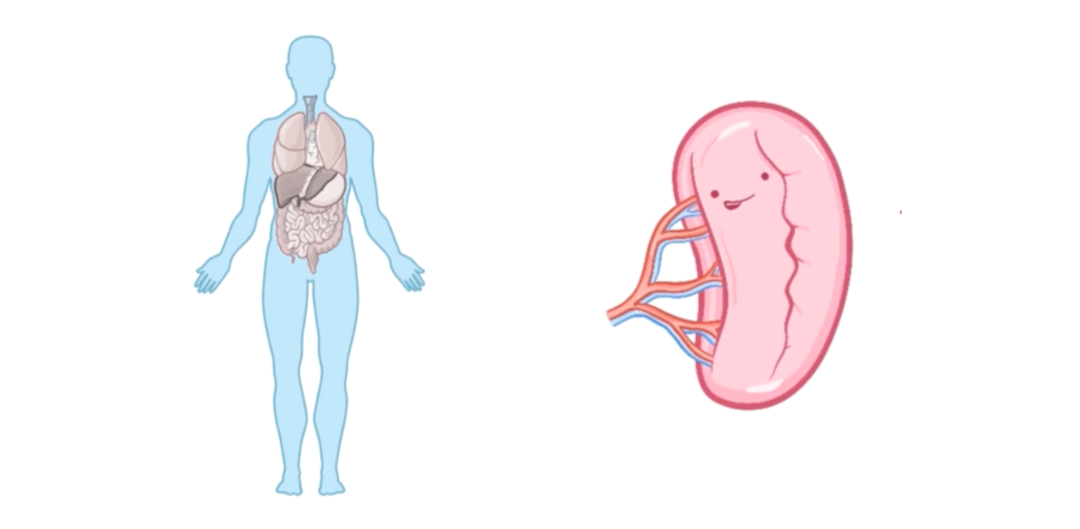

由肺炎链球菌引起的败血症在脾脏功能异常的人群中尤为常见,因为脾脏在免疫中发挥着重要作用,尤其是对有荚膜的细菌。

因此,肺炎链球菌感染在接受过脾切除术(即切除脾脏)的患者,或在镰状细胞病患者中表现得更为严重,因为后者存在功能性无脾。